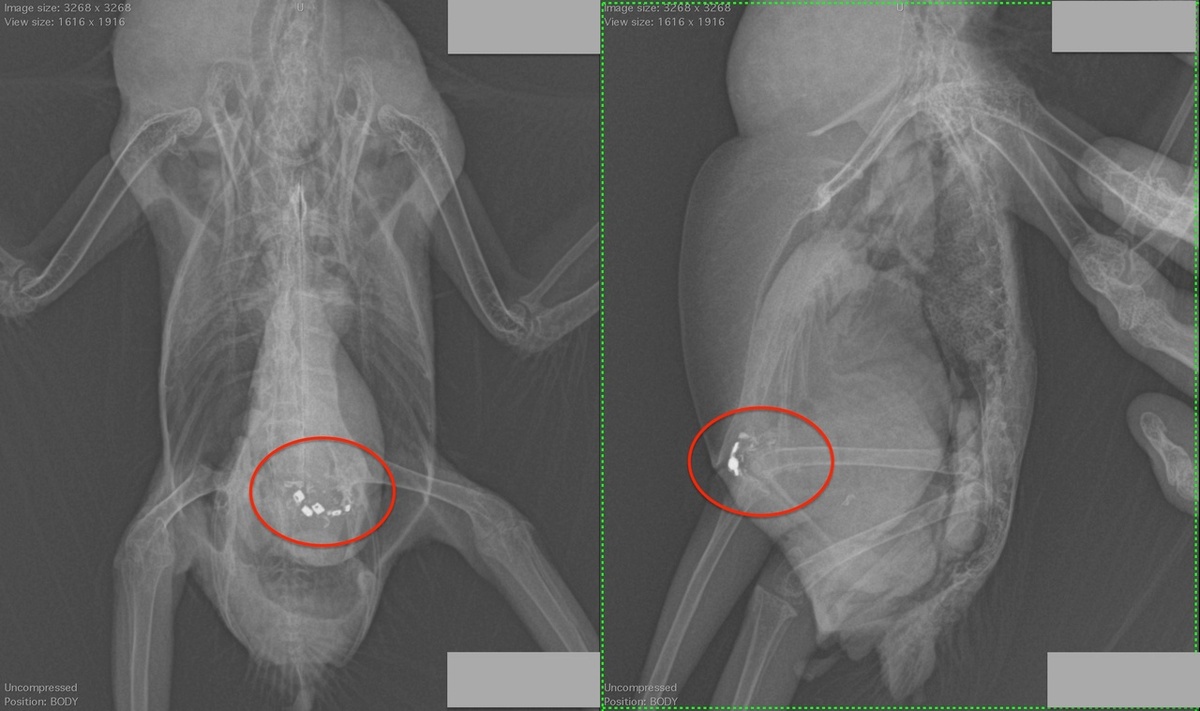

В этом случае, жако погрыз кнопки от пульта, их остатки хорошо видны на рентгене.

на рентгене этого жако  в мускульном желудке видны кнопки от пульта, раздутый зоб и желудок. Кроме того, видна пневмония и другие проблемы, которые были у попугая до отравления свинцом.